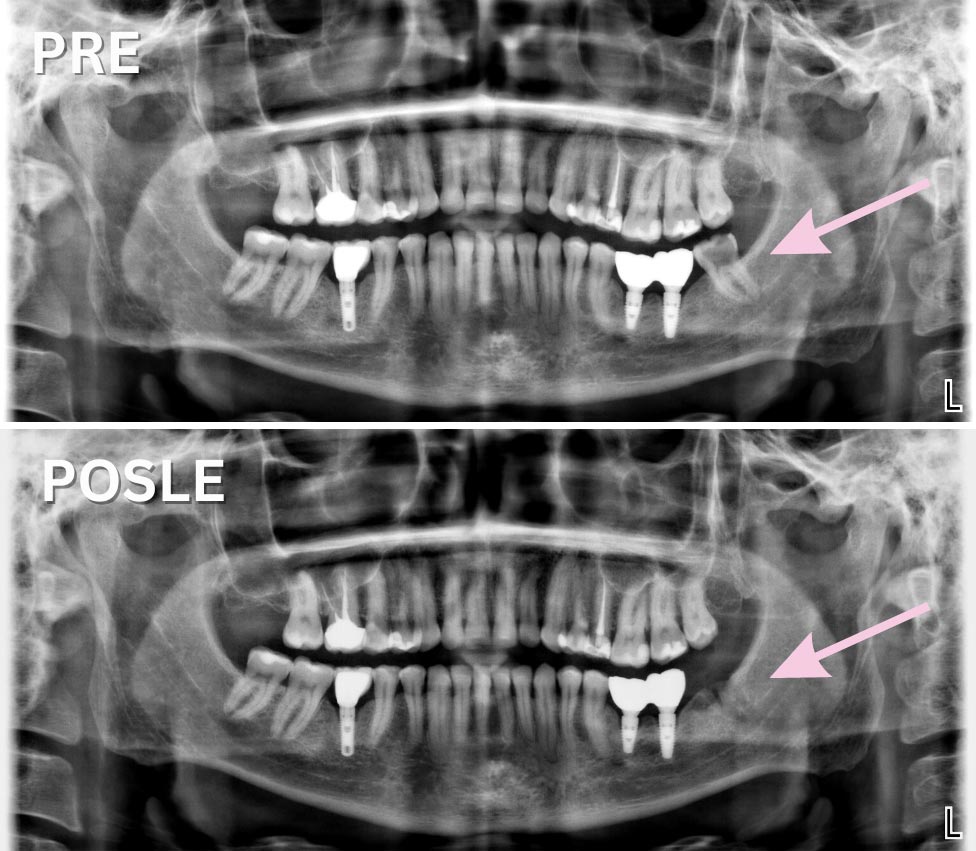

Vađenju zuba obavezno prethodi stomatološki pregled i RTG snimanje zuba. Snimanje se obavlja u rendgen-kabinetu na našoj klinici, što u mnogome ubrzava postupak i pacijentima olakšava situaciju.